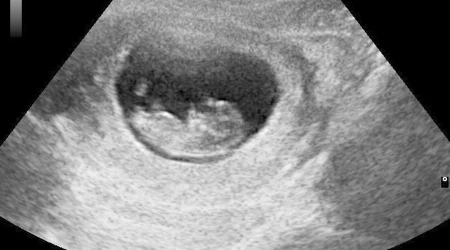

"Mientras tanto, estados como el nuestro han aprobado leyes muy intencionales relacionadas con cosas como el consentimiento informado y los ultrasonidos realizados con antelación", dijo Bevin.